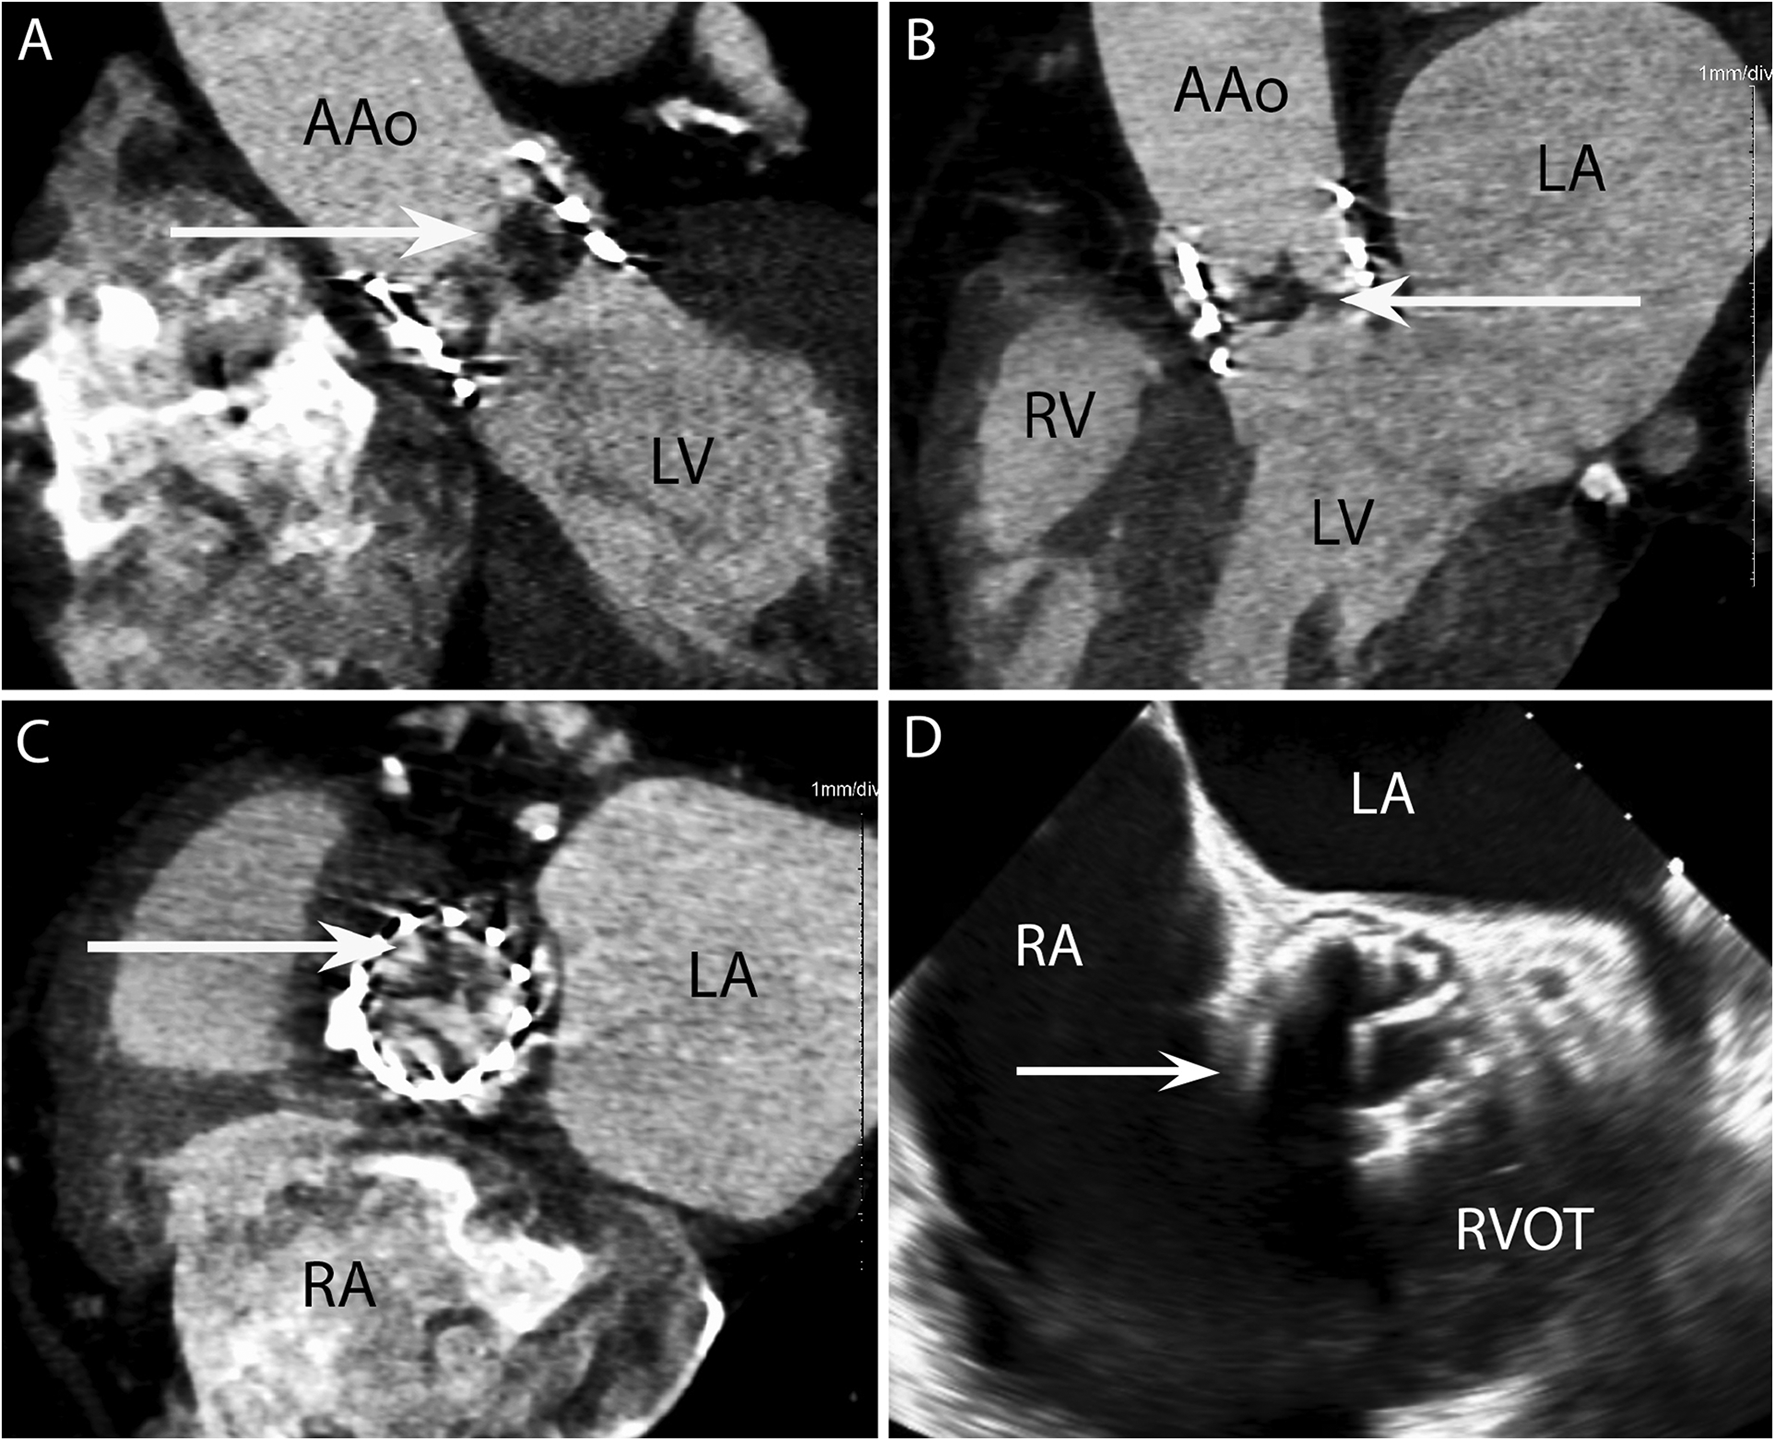

Figure 2

CASE 2 - A 77-year-old man with a history of transcatheter aortic valve implantation (TAVI) presented with a sore throat, diarrhoea, and a temperature of 40°C. Staphylococcus aureus was isolated from blood cultures (see text). RA, right atrium; RVOT, right ventricular outflow tract; RV, right ventricle; LA, left atrium; LV, left ventricle; AAo, ascending aorta.

A 77-year-old man with a history of transcatheter aortic valve implantation (TAVI) presented with a sore throat, diarrhoea, and a temperature of 40°C. Staphylococcus aureus was isolated from blood cultures. Cardiac CT was performed within 24 h. The oblique coronal (Figure 2A) and 3-chamber (Figure 2B) views demonstrated a low-density soft tissue vegetation (arrow) with a Hounsfield Unit (HU) value 80 attached to the TAVI leaflets. An in-plane view (Figure 2C) showed that the vegetation (arrow) involved all three cusps of the implanted valve. In the initial TOE images (Figure 2D) taken in the ME AV SAX view, the TAVI nitinol stent frame obscured adequate prosthetic valve leaflet evaluation (arrow) and aortic root involvement could not be established.

Case 3

A 79-year-old man presented with shortness of breath and fever. Blood cultures grew Staphylococcus aureus. The axial 4-chamber (Figure 3A) and oblique sagittal 2-chamber (Figure 3B) views demonstrated a low-density soft tissue (HU 78) vegetation (arrow) attached to a calcified posterior mitral valve leaflet. An oblique coronal view (Figure 3C) confirmed these findings and highlighted possible involvement of the anterior leaflet. Preceding TOE images in the mid-oesophageal (ME) 4-chamber (Figure 3D), ME 2-chamber (Figure 3E) and ME 3-chamber (Figure 3F) views demonstrated a large heterogenous calcified mass attached to the posterior mitral valve leaflet (arrows) consistent with a vegetation. A possible paravalvular pseudoaneurysm with disruption at the LA free wall (asterisk) was noted but was excluded on subsequent CT.